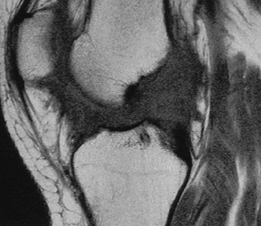

![]() |

FIGURE 5-58 MR images of osteochondritis dissecans in two different patients. T2-weighted sagittal (A) and axial (B) images showing a large defect with high-intensity fluid (arrows) separating the fragment from the condyle. This is an unstable lesion. (C) Sagittal T2-weighted image in a different patient showing abnormal signal intensity (arrows), no fluid line around the lesion, and intact cartilage. This is a stable lesion.